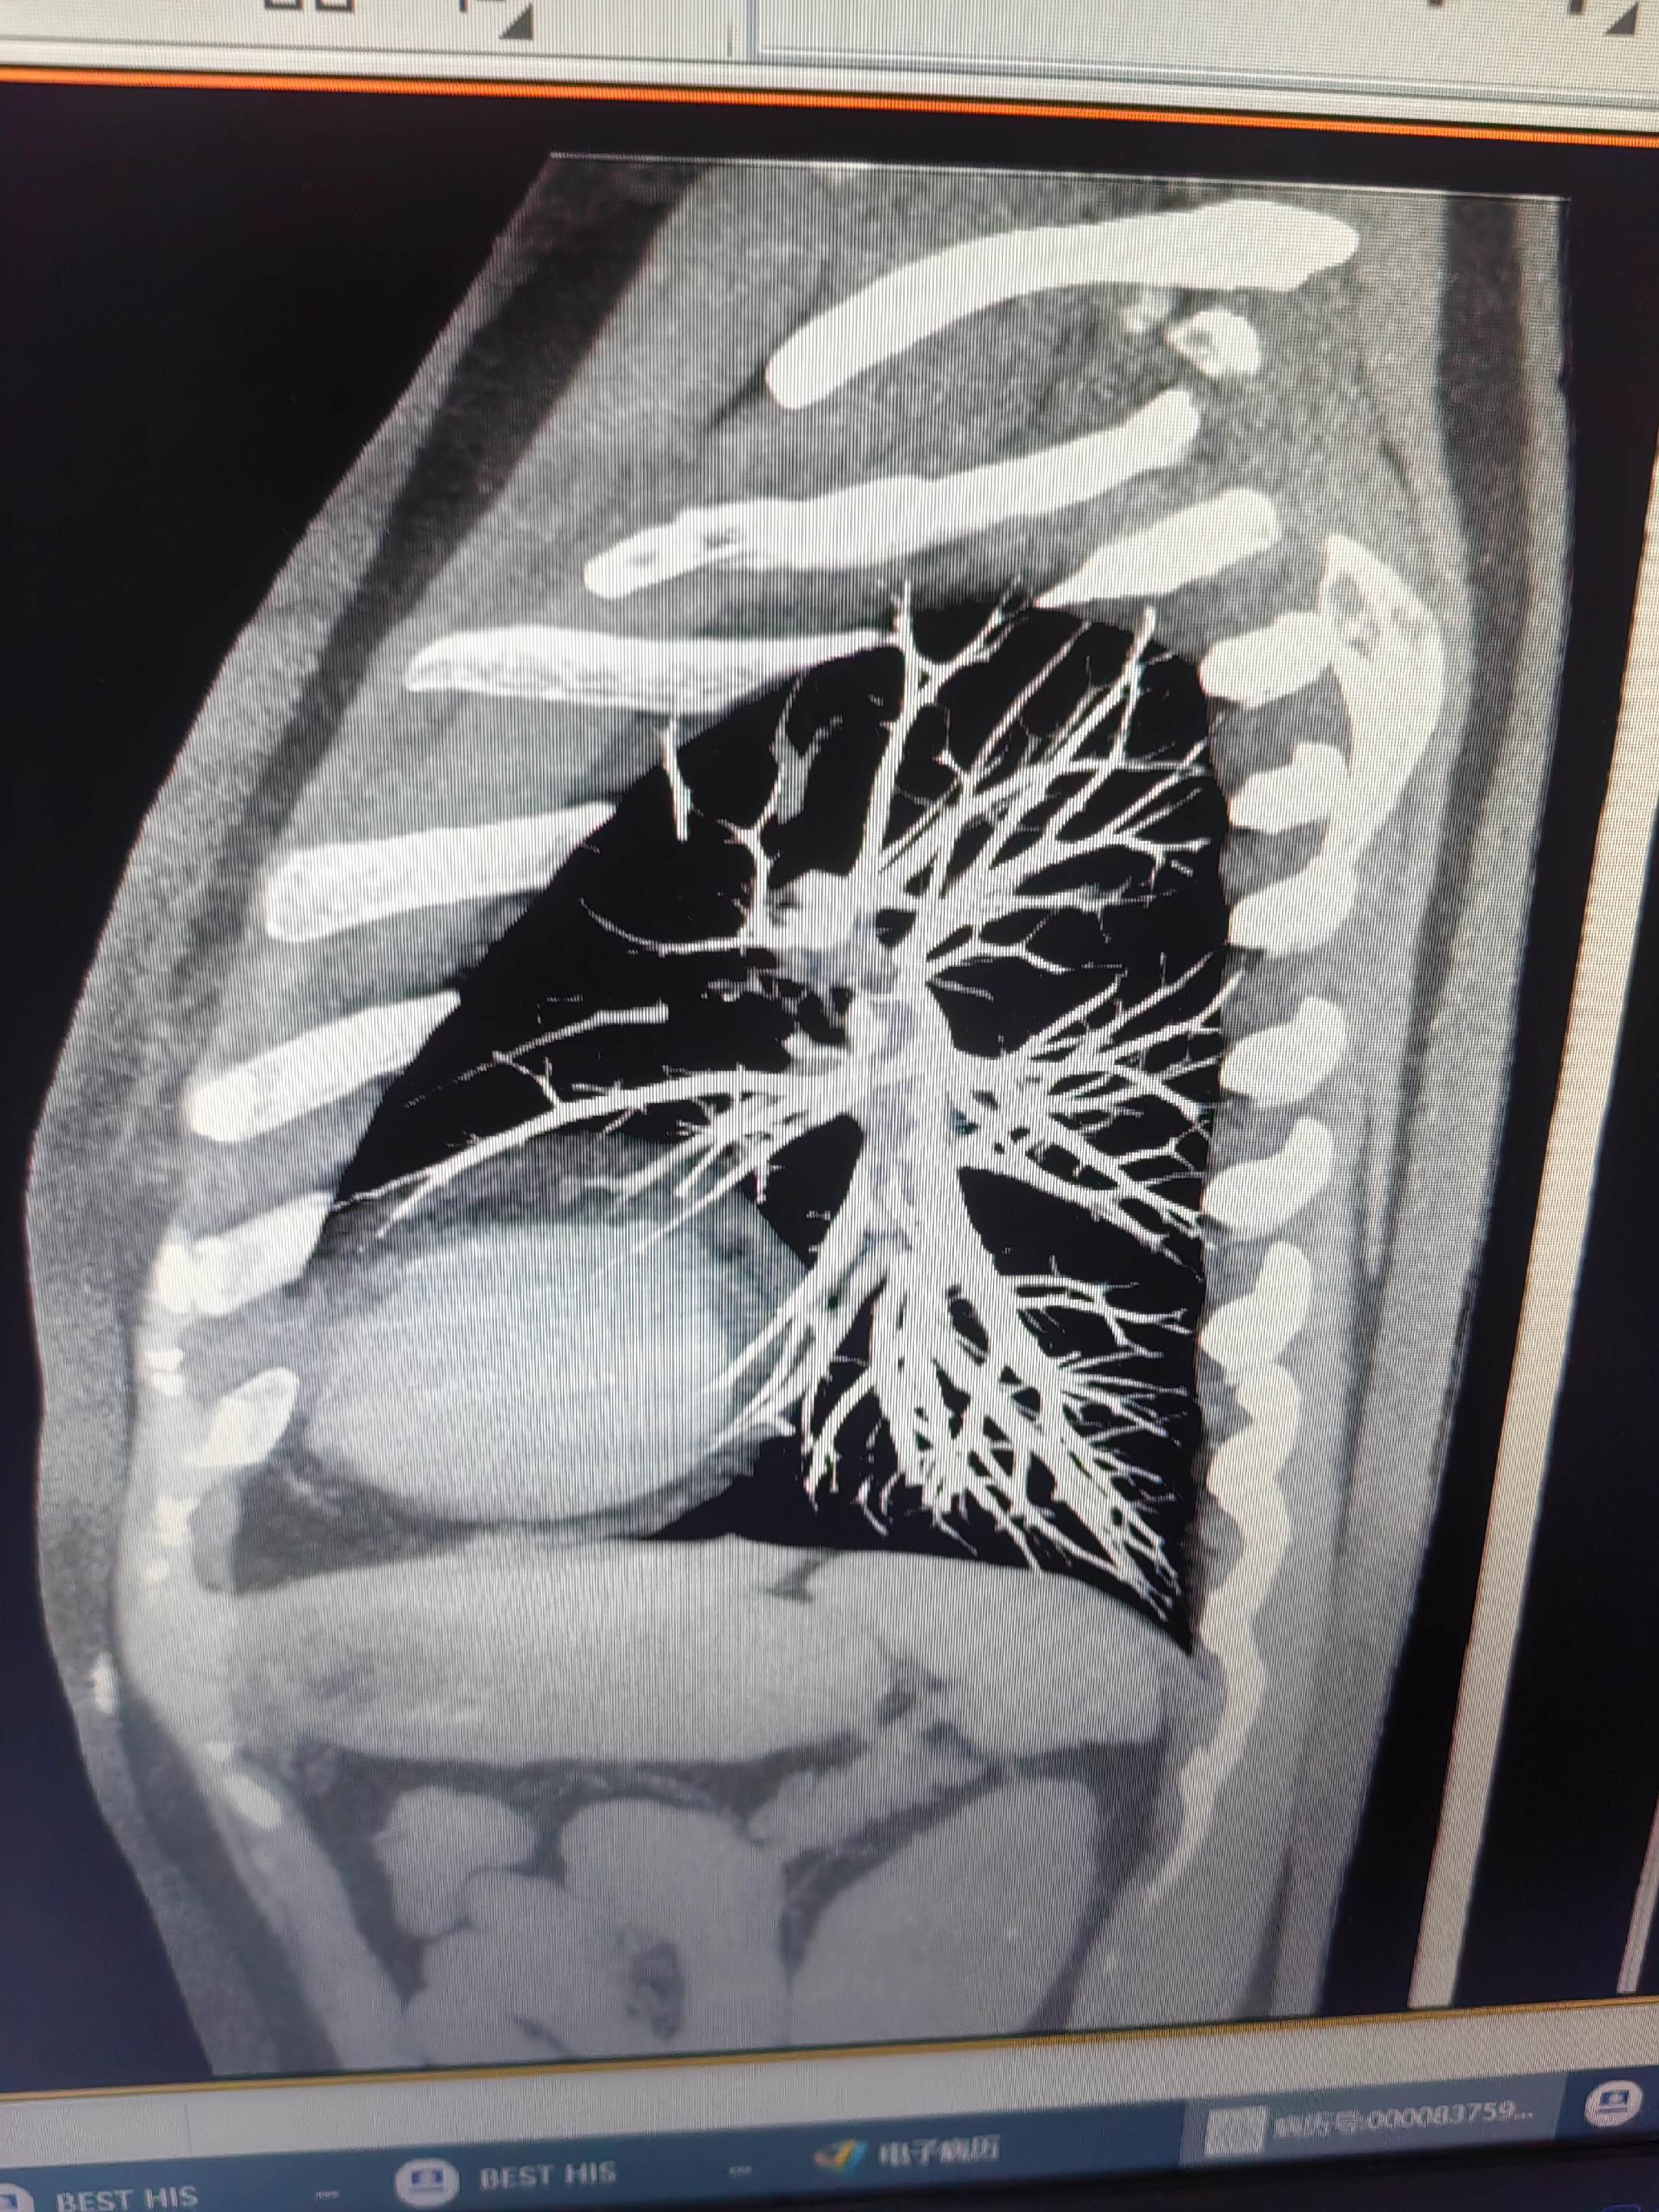

肺栓塞。